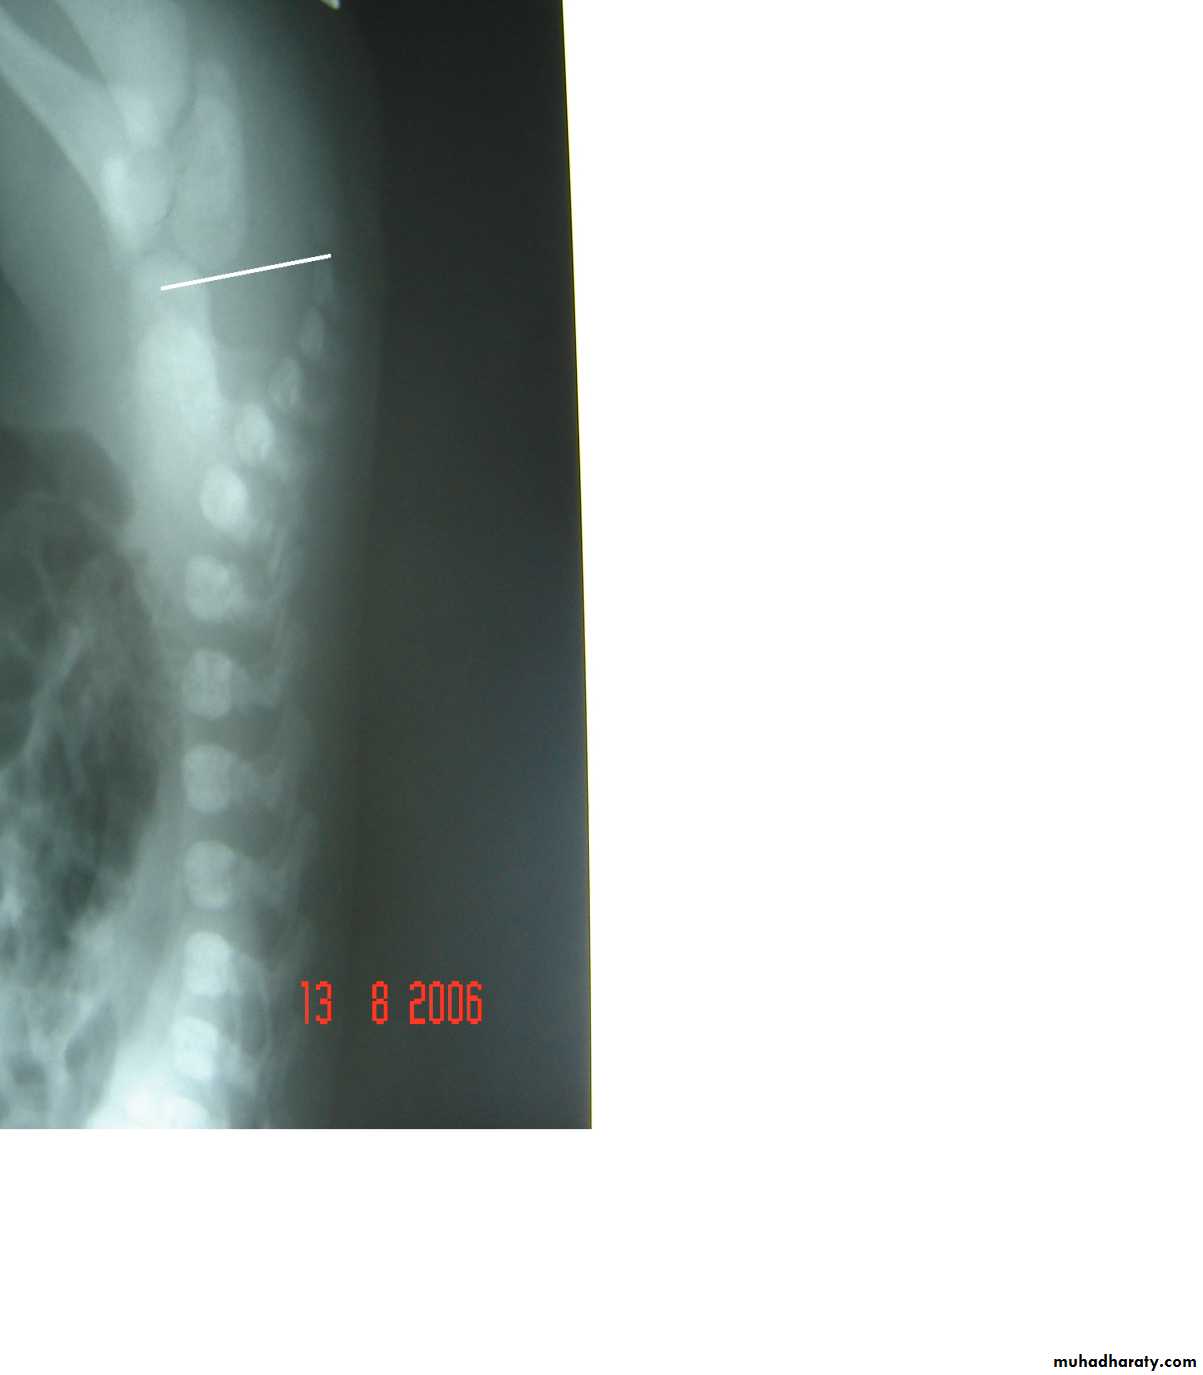

Oesophageal Atresia and Tracheo-Oesophageal Fistula,